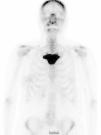

The study of the extension of the disease included BS, which revealed the presence of a diffuse blastic lesion in the sternal manubrium, suggestive of Paget's disease or a metastatic lesion (Fig. 1). The study was completed with radiographs of chest, lumbosacral spine and pelvis (Figs. 2 and 3), in which the only finding was increased density in L4-L5 facet joints. Chest CT, recommended by the professionals in nuclear medicine, revealed sclerosis in the sternal manubrium, suggestive of metastasis (Fig. 4).

Laboratory findings included normal values for alkaline phosphatase (95IU/L), calcium (9.57mg/dL), lactate dehydrogenase (161IU/L) and erythrocyte sedimentation rate (6mm). Only a slight increase in C-reactive protein (0.60mg/dL) was observed. A test for HLA-B27 was not requested because of the negative results in the laboratory tests and the limited relationship to SAPHO syndrome reported in some case series.9

Given the difficulty of the case, a clinical discussion session was held, with the participation of the departments of radiation oncology, rheumatology, radiodiagnostics and nuclear medicine, to review the findings. The outcome was a definitive diagnosis of SAPHO syndrome, as the patient met one of the inclusion criteria described by Benhamou et al.,5 hyperostosis of anterior chest wall, with or without dermal involvement, and none of the exclusion criteria (Table 1). A biopsy of the lesion was ruled out at that time, pending the radiographic evolution. The decision was made to perform BS and osteoarticular CT11 6 months later, at which time, no noteworthy changes were observed, and a biopsy of the affected area was definitively ruled out, as the images showed no signs of aggressive disease. During treatment, the patient required no analgesic medication of any type. We excluded the affected area from the field of treatment to avoid provoking modifications secondary to the radiotherapy that could lead to confusion when assessing the changes in the lesion. After 18 months of follow-up, the complete response of the tumor persists and the patient is disease-free.